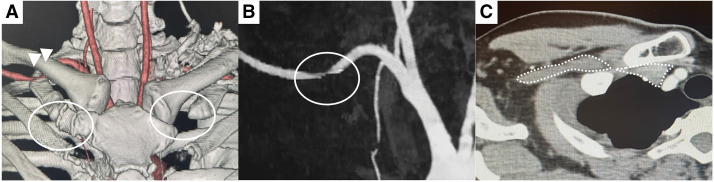

A 41-year-old woman with a 1-year history of right chest pain, with normal cardiology and pulmonology assessments. The chest pain was reproducible upon upper limb elevation. Computed tomography (CT) angiography in the arm-elevated position revealed subclavian artery and vein stenosis at the costoclavicular space, and the diagnosis was neurogenic thoracic outlet syndrome (TOS). Surgery involving endoscopic-assisted infraclavicular resection of the first rib and scalene muscles resulted in immediate postoperative symptom improvement. When chest pain persists after ruling out other conditions, neurogenic TOS should be considered in the differential diagnosis.